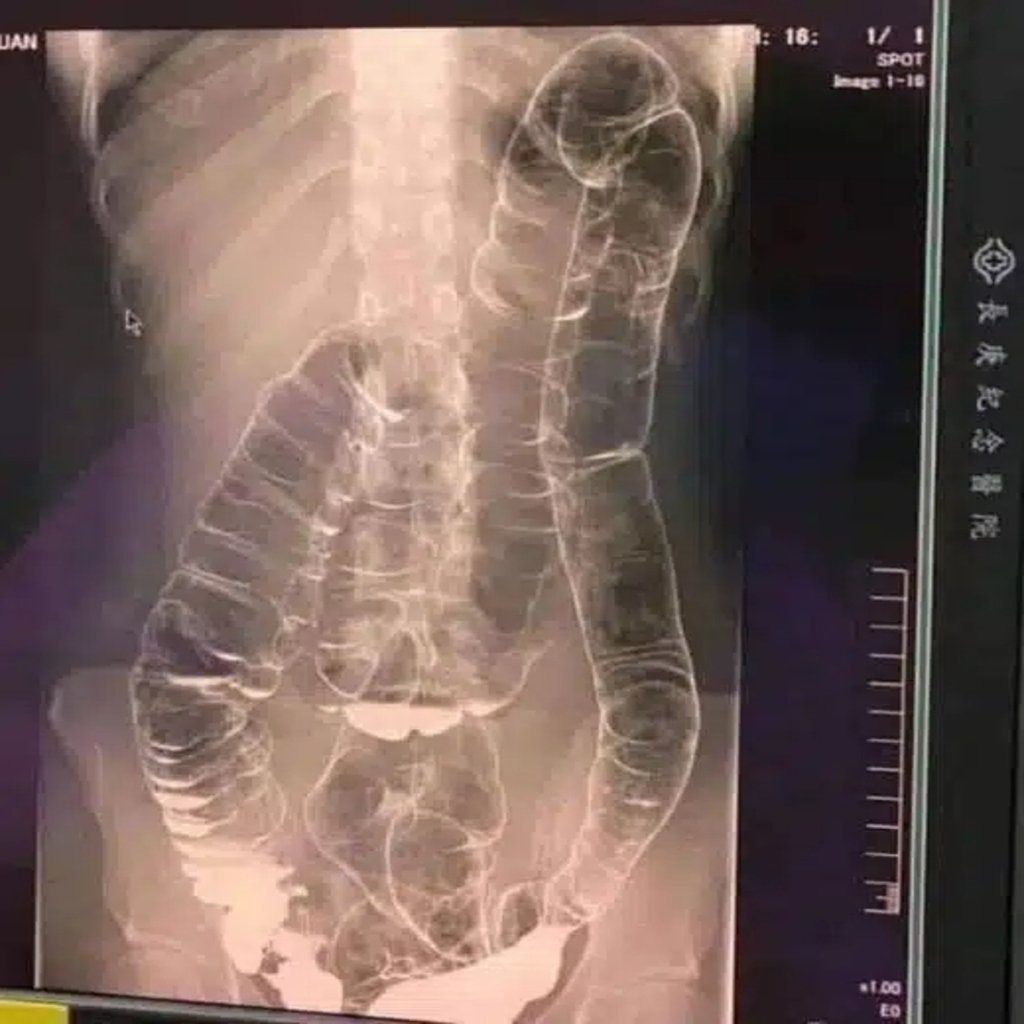

Cólon saturado: quando o corpo dá sinais de alerta

Cólon Saturado: Quando o Corpo Dá Sinais de Alerta A constipação intestinal, muitas vezes vista como um incômodo passageiro, pode ser um sinal de alerta para problemas mais sérios. A sensação de intestino preso, quando frequente ou prolongada, indica que algo não está funcionando corretamente no seu sistema digestivo. Neste artigo, vamos explorar as causas, … Leia mais